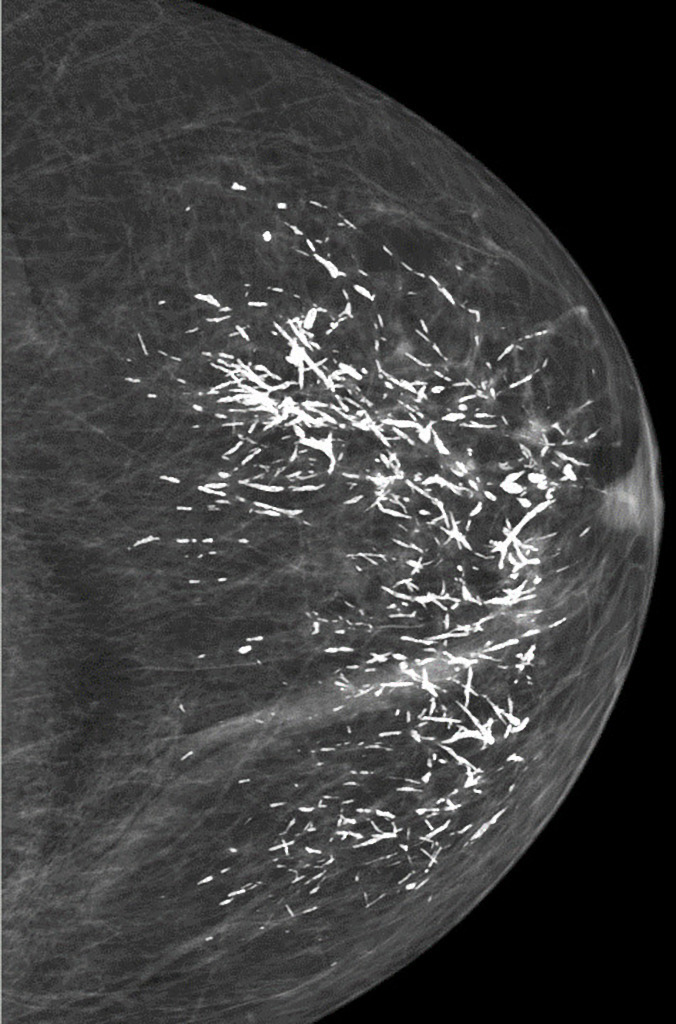

Linear, thick, ‘rod-like’ calcifications in both breasts, with a symmetrical distribution. Typical appearance of plasma cell mastitis (BI-RADS 2, benign).

Predominantly fatty breast tissue. No further findings.

Plasma cell mastitis has a characteristic appearance. Calcifications are thick, linear, rod-like or cigar-shaped. Calcifications can be up to 10 mm long. They tend to be bilateral, often symmetrical in distribution and oriented with long axes pointing toward the nipple1. Branching may sometimes be seen.

Compared to microcalcifications of DCIS or ductal carcinoma, calcifications of plasma cell mastitis are larger in both length and caliber and have a smoother outline.